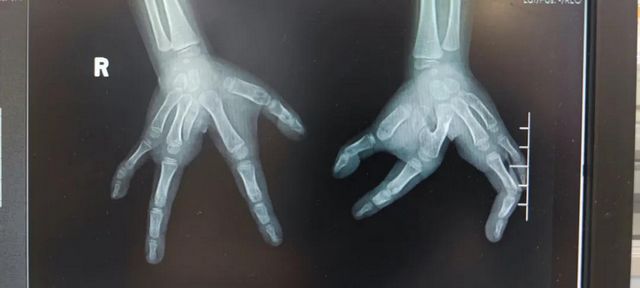

12月2日,一位年仅4岁半的小女孩,在西南医大附院康健中心院区,经历5个小时手术后,原本分开的手指成功地合上了。主刀医生叶里子表示,像这样的先天性分裂手(俗称龙虾手),在世界范围内都非常罕见,平均每一百万人中仅有4例。

“从一出生,孩子的双手就像是一把‘剪刀’,不仅没有中指,四指还无法合拢”。几天前,家住叙永县的王先生带着四岁半的女儿来到西南医大附属医院康健中心院区小儿外科,小女孩十分文静乖巧,总是躲在父亲后面。当孩子摊开两只小手,现场的医护人员大吃一惊:双手的四根手指“分居”两侧,如一把打开的“剪刀”。

经历大约5个小时的紧张手术后,叶里子的话让王先生咧开了嘴。“手术很成功,四根手指回归原位并伸缩自如,双手功能可以达到正常人的90%以上,预计下周一就能出院。”

叶里子介绍到:先天性分裂手是一种手发育畸形,主要表现为缺少中指,中间的手掌向两边分裂。属于基因性突变,成因较为复杂,并不一定是遗传,也可能是在怀孕期间,摄入了一些不良的病菌、气体、辐射等,甚至有可能是因为饮食和生活上的不注意造成的。